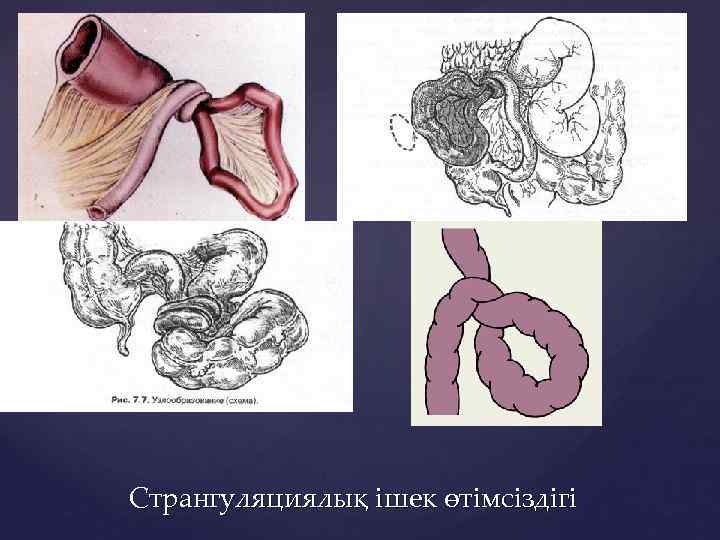

Странгуляцияға ішек бұралуы, байлануы, қысылуы, күрмелуі себеп болады. Обтурациялық түрінде ішек ісікпен, аскаридамен, дәкелі құрғатқыш (операцияда ұмытылған) бітеледі. Қан айналысы онша бұзылмайды. Өйткені шажырқай қысылмайды. Ішек түйілуінің келесі себебі инвагинация - ішекке ішек еніп оның бітелуіне қоса шажырқайдың қысылып, қан айналысы бұзылуы байқалатындығынан илеустің бұл түрінде обтурация және странгуляция қоса байқалады. Ішектің қабырғасының тегіс етінің әлсізденуіне байланысты кездесетін ішек түйілуі динамикалық деп аталады. Илеустің бұл түрін тырысқан және салды деп екіге бөледі. Спастикалық түрі - ішек қабырғасының тырысуынан оның өзегі тарылуымен байланысты болса, паралитикалық илеусте ішек созылған, өзегі кеңіген, оның тонусы - қозғалуы нашарланған.

{ Схематическое изображение инвагинации тонкой кишки в слепую — двойная инвагинация { Схематическое изображение инвагинации тонкой кишки в слепую — одиночная инвагинация Инвагинация

. Ащы ішектің (заворот) айналуы . Ішектің ішекке енуі – (инвагинация).